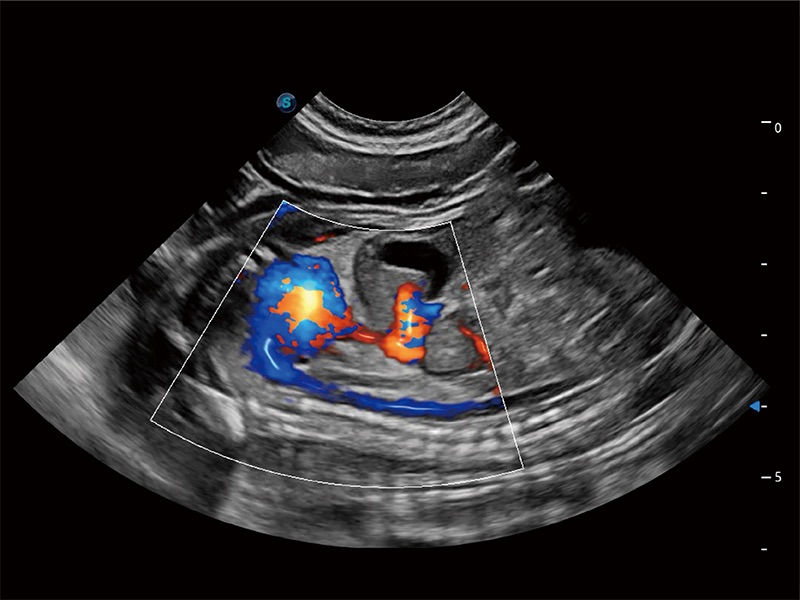

高性能和先进的临床应用工具可以为动物医生提供临床信心。ProPet 80 搭载了先进的腹部和浅表应用工具,帮助医生在日常临床实践中发挥前所未有的作用。

极大提升超低速微细血流的检出能力,同时更精准地滤除软组织和超声信号,为兽用医生提供以往无法通过常规血流获得的疾病诊断信息。

在传统二维血流成像的基础上,呈现血流的立体感,具有动感的生命力之美。即便是微小的血管也能轻松应对,提高了血流的视觉敏感性。